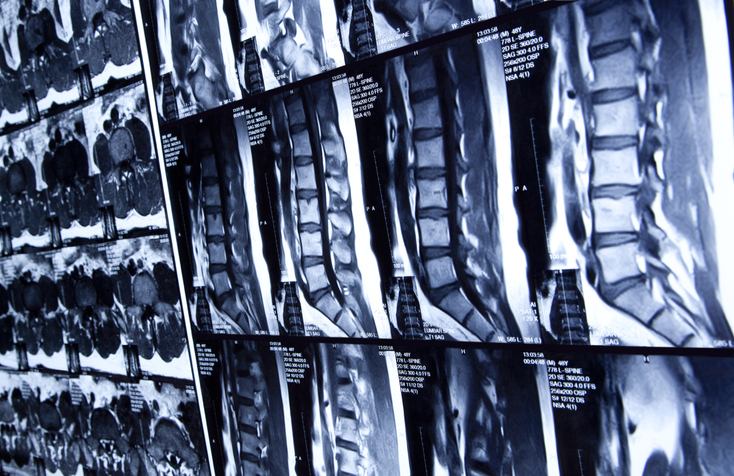

State-of-the-art expertise in treating brain tumors, spinal disorders, cancers, vascular issues and other complex neurological conditions.